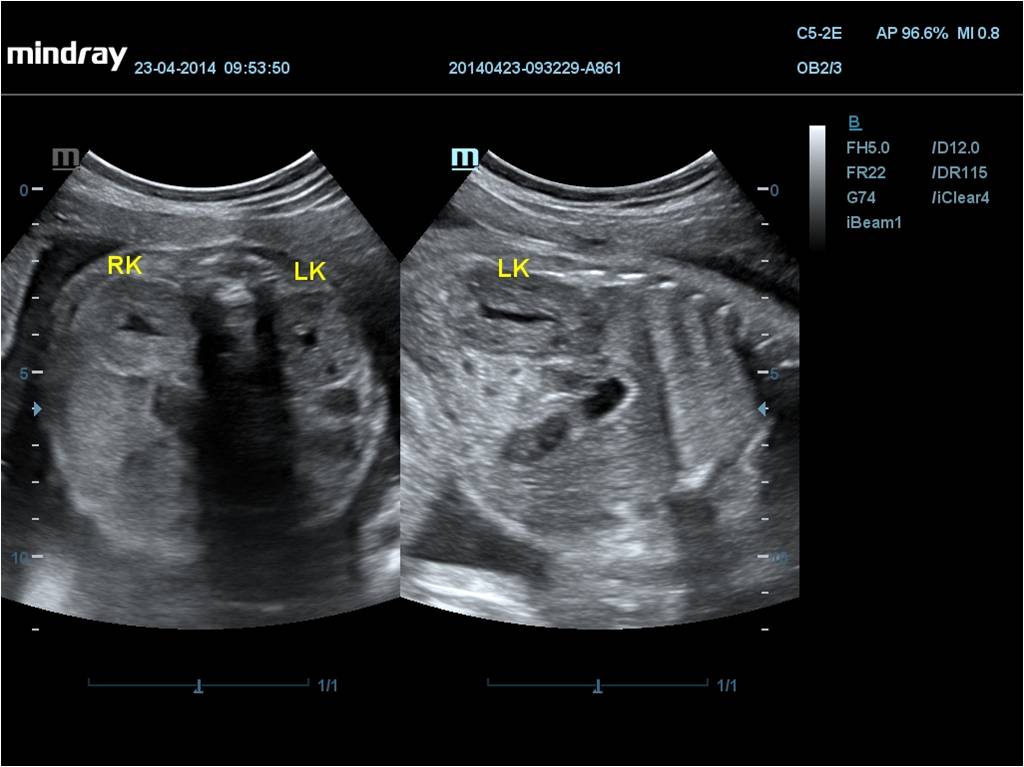

• Общая визуализация

• Гинекология и акушерство